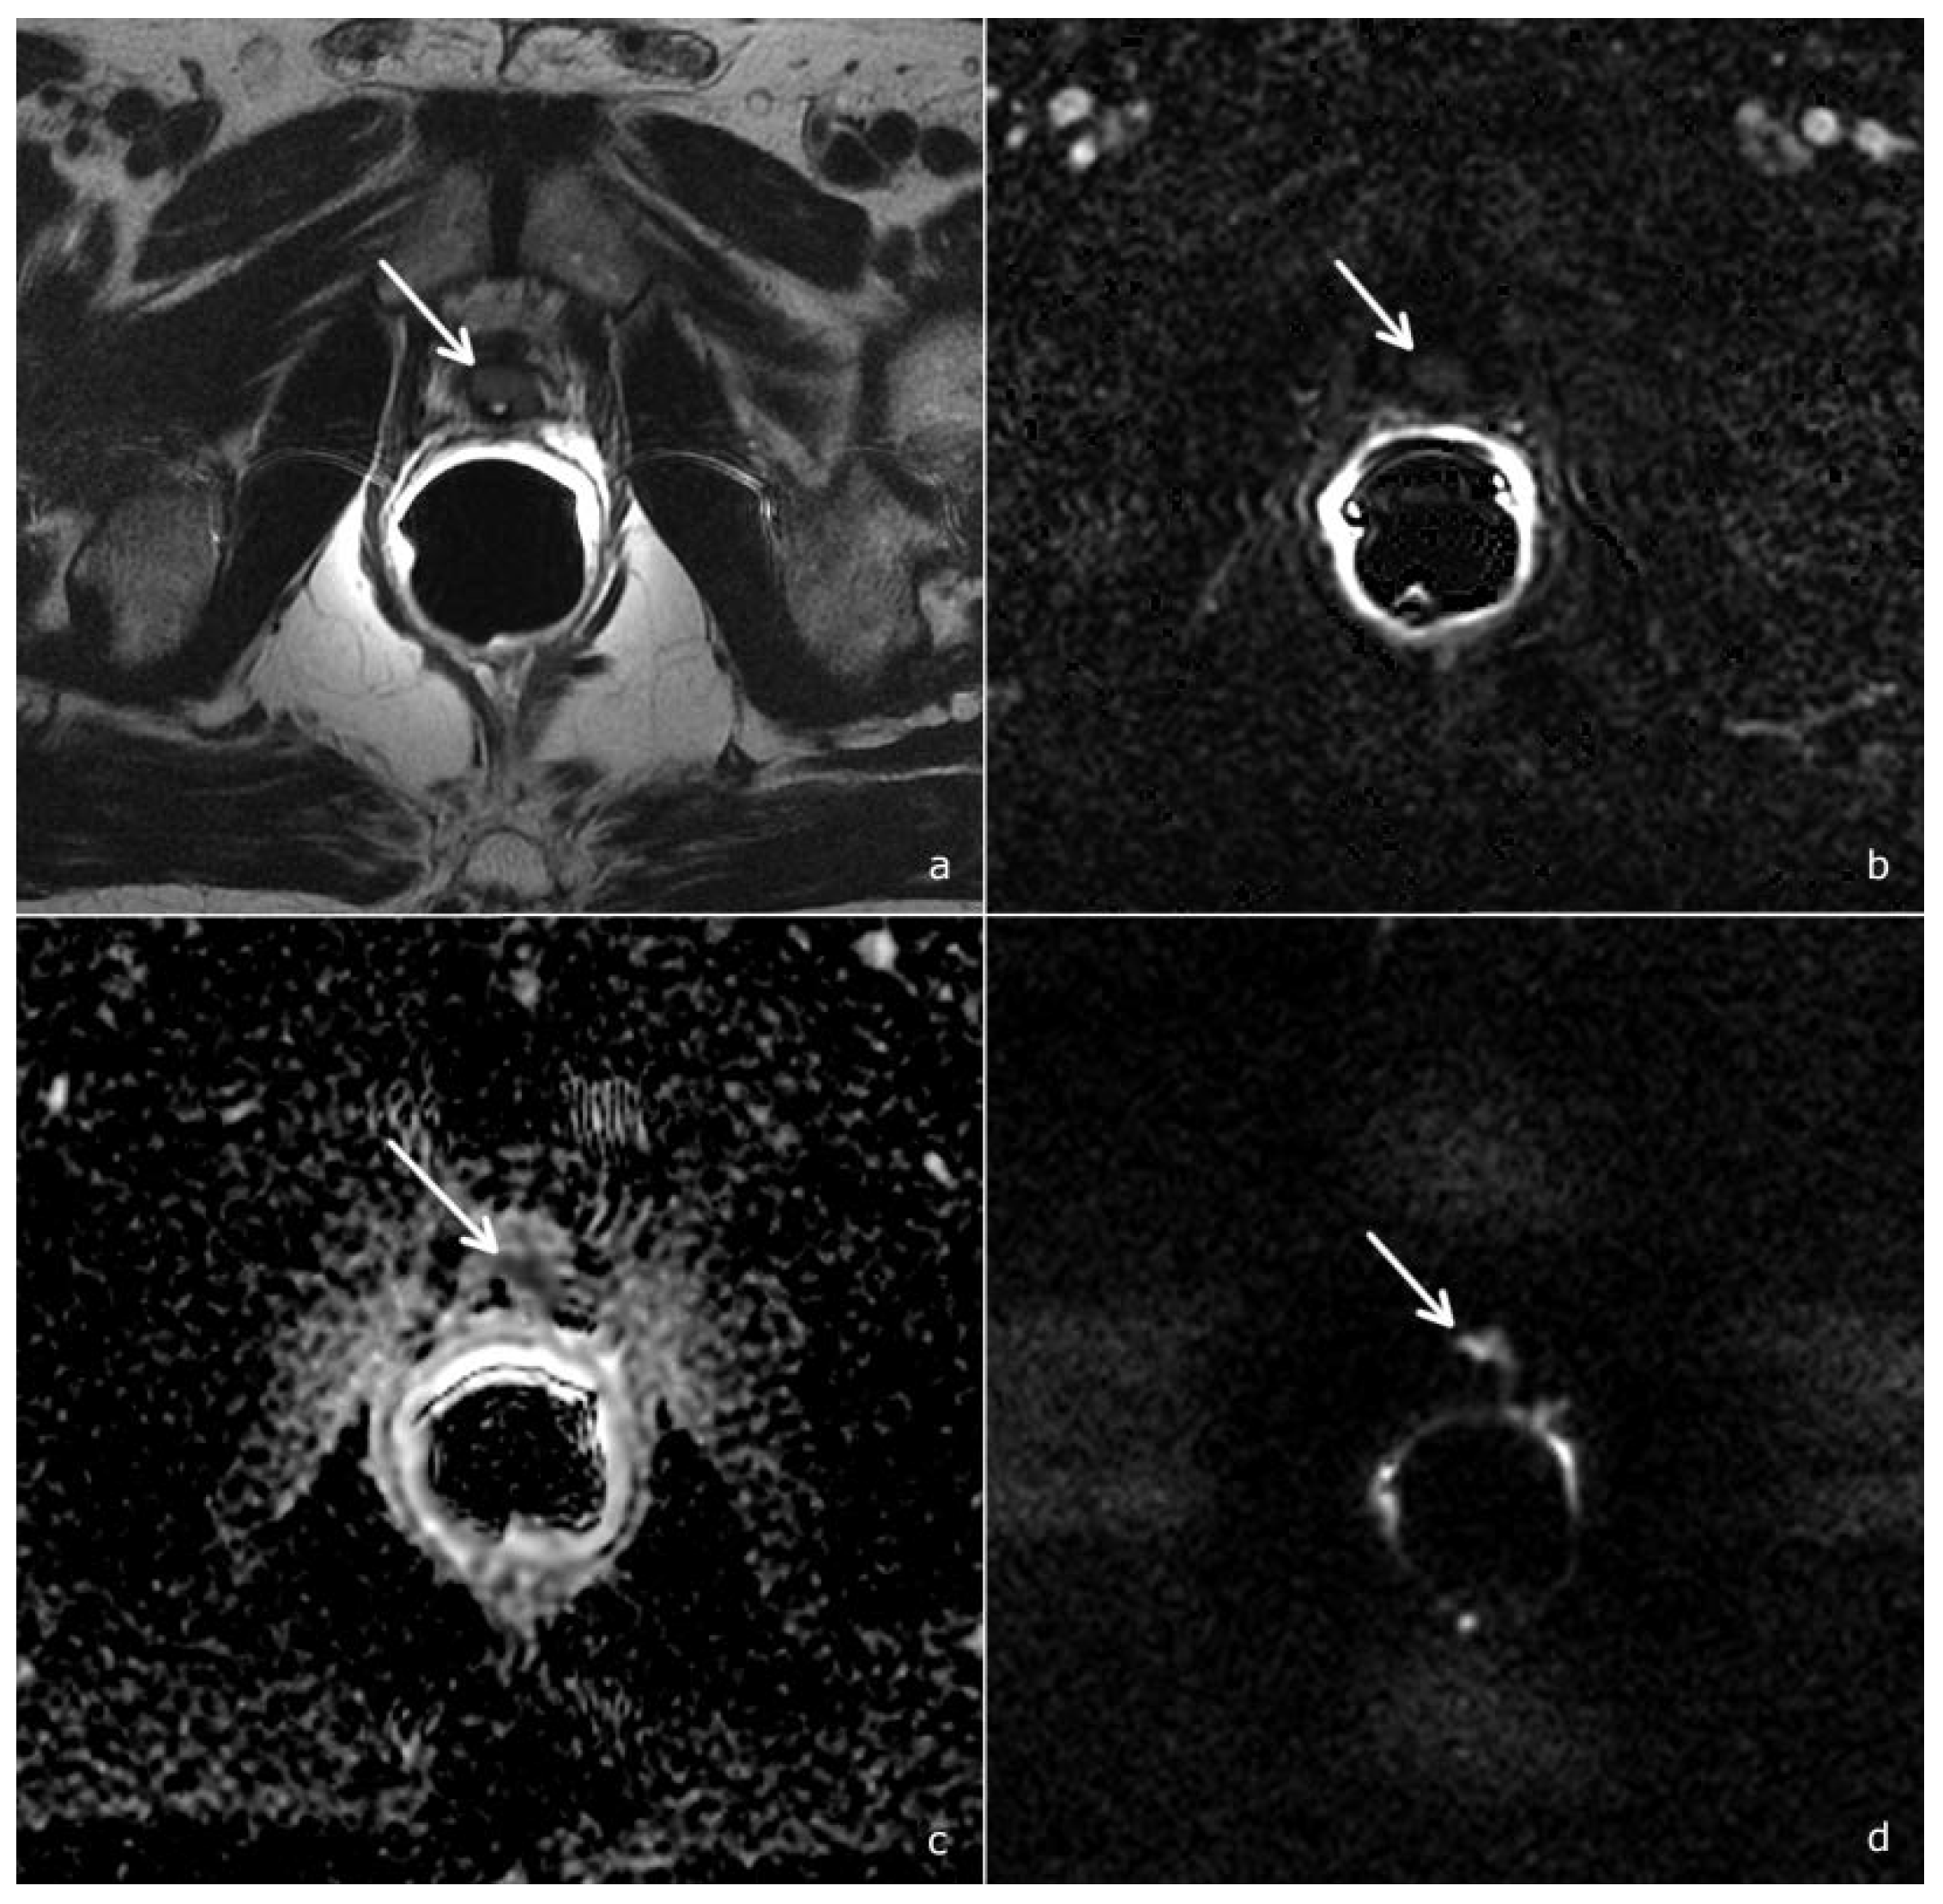

Several studies addressed the value of mpMRI in the detection of local recurrence, pointing out the key role of perfusion-weighted imaging [15,16,17,18]. Taking into account these results, the PI-RR score was assessed considering DCE as the dominant sequence guiding the overall assessment score: at DCE imaging, local recurrence shows a rapid and early enhancement, with a kinetic different from that of post-operative fibrotic changes (which either do not enhance or enhance slowly and homogenously) [8], Figure 3.

Figure 3.

A PI-RR-score-2 patient, 68 years old, with a PSA value of 0.45 ng/mL. (a) T2-weighted image shows a hyperintense tissue in the rectovesical region (arrow), characterized by a homogeneous and diffuse contrast enhancement, (b) non-pathological signal abnormality on the ADC map, (c) slightly hyperintensity on DWI, (d) a TRUS-guided biopsy was performed, documenting benign prostatic tissue remnants.

Also a recent study by Gaudiano et al. demonstrated that the specificity of mpMRI could be improved through the analysis of signal intensity/time curves: indeed, while benign tissue is most frequently associated with a type 1 curve, recurrences generally show type 2 and 3 curves [19]. Combining DWI to DCE imaging further increases the diagnostic accuracy of mpMRI and allows the upgrading from PI-RR 2 to PI-RR 3 and from PI-RR 3 to PI-RR 4 if the DWI score is superior or equal to 4 [8], as shown in Figure 4.

Figure 4.

A PI-RR-score-4 (arrows), in a patient 72 years old, with a PSA value of 0.71 ng/mL. (a) T2-weighted image documents hypointense tissue localized anteriorly to the vesico-urethral anastomosis. (b) DCE depicts a focal mild and late enhancement. However, as the ADC map (c) and DWI (d) show a significant diffusion restriction (DWI score = 4), the overall PI-RR score was 4.